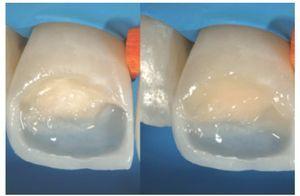

Figura 18a y b Para conseguir una restauración estéticamente atractiva es importante controlar de forma concienzuda las capas de dentina y esmalte.